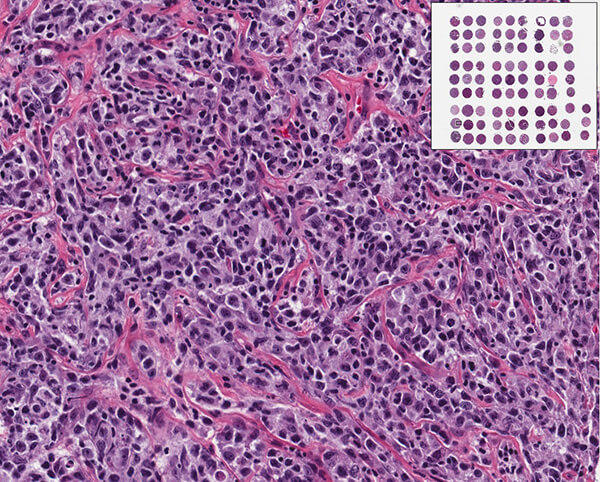

AIDS lymphoma tissue micro-array and a photomicrograph of AIDS lymphoma.